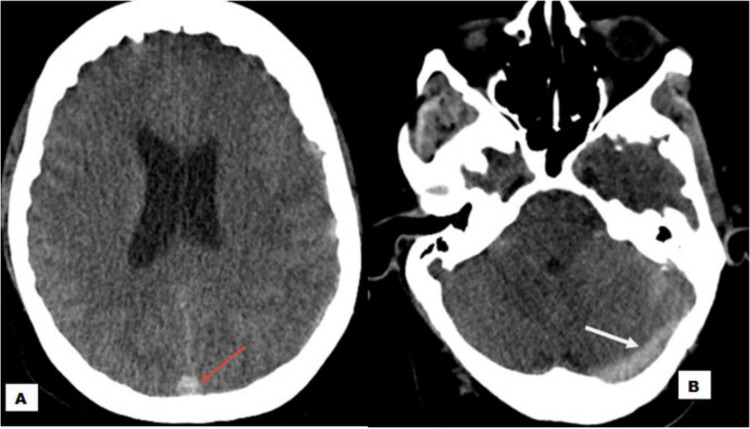

Cerebral sinus venous thrombosis (CSVT) is an uncommon and potentially life-threatening neurological disorder that is often missed because its clinical and radiological symptoms are not specific. Snake bites are a rare cause of cerebral venous sinus thrombosis that must be recognized and treated promptly to improve survival. Here, we present a case of a 30-year-old male patient who had cerebral venous thrombosis after snake bite in the rural area of southern Somalia. After close monitoring with anticoagulation, the condition of the patient improved and discharged from the hospital with full of consciousness. There are only a few cases reported in the literature of snake bites causing cerebral venous thrombosis.

Abstract Image